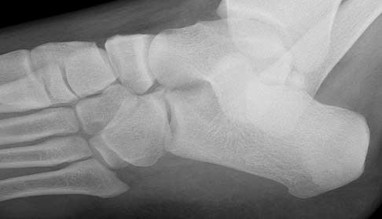

QUESTION 3

Figures 3a through 3h

1

Normal foot

2

Calcaneonavicular (CN) coalition

3

Talocalcaneal (TC) middle facet coalition

4

TC posterior facet coalition

- TC posterior facet coalition

Figure 3a shows a flatfoot. Figure 3b shows an MF and TB, but not a C sign. Figure 3c shows a bony irregularity between the calcaneus and the navicular and a WN. Figure 3d shows an MF. Figure 3e shows an MF, but narrowing or loss of the posterior facet. Figures 3f through 3h show medial edema and joint irregularities consistent with a posterior facet coalition.